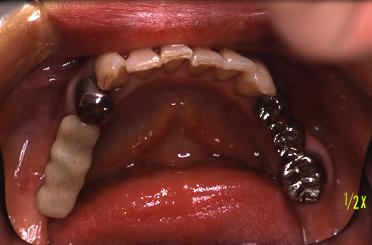

術前

右下奥歯3本の歯がないです